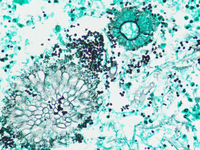

Invasive Aspergillosis in bone marrow - PAS stain 2

Category: Infectious Disease > Fungi > Aspergillus

Periodic Acid Schiff stain showing septate fungal hyphae and conidia (PAS, 400x)